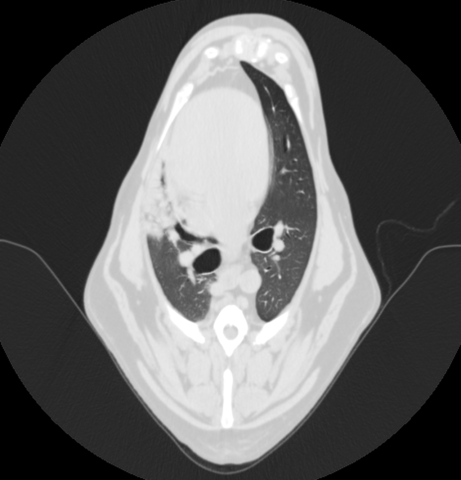

また右肺中葉全域と左肺前葉腹側の一部が無気肺になっていた。

以上の結果から、異物誤飲による腸閉塞、またそれによる嘔吐・吐出により、誤嚥性肺炎を引き起こしていると診断した。